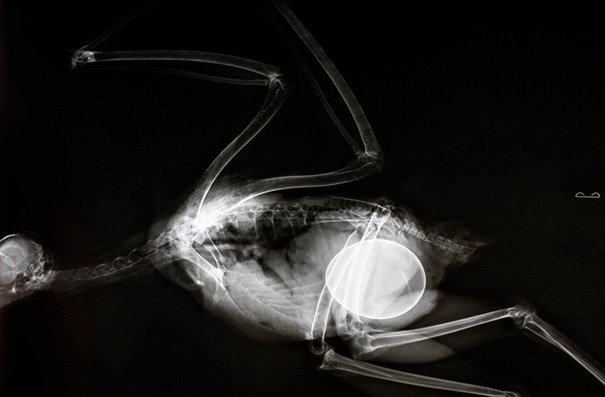

киви